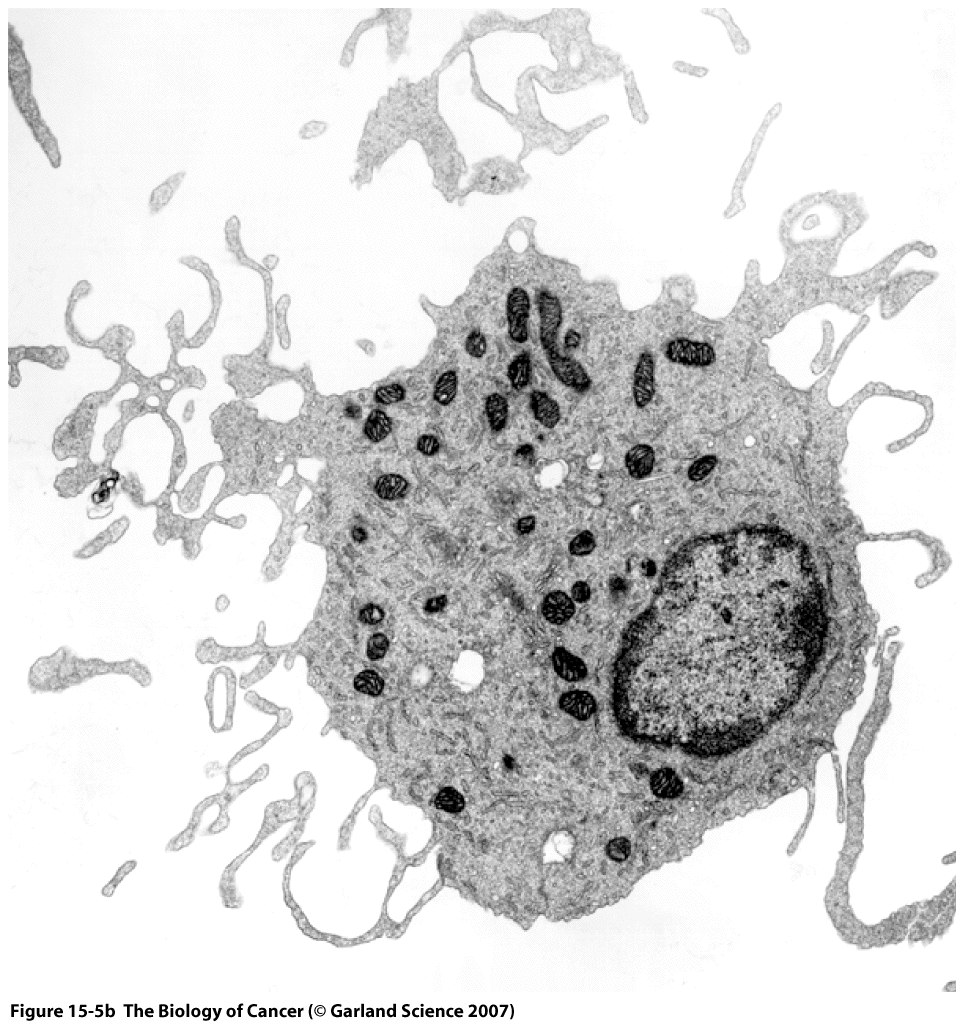

This Concept Map, created with IHMC CmapTools, has information related to: Chapter 15 Merged Map, tumor-specific transplantation antigens (TSTAs) may confer cross-immunity, inflammatory response as facilitated by tumor-associated macrophages (TAMs), Immune System (15.1) lead to Immunosurveillance theory (Section 15.7), immune system with cells such as macrophages, MHC class 1 molecules may attract cytotoxic T cells, Cytotoxic T cells can cause sutoimmune diseases, normal oligopeptides result in tolerance, holes in memebrane allow entrance of granzymes, allograft rejection truly due to cells being from different species, tolerance as oppose to self reactive lmphocytes, innate immune response is the sole respone in 99% of animal species, helper T cells release cytokines, Regulatory T cells express FOXP3 transcription factor, helper T cells activate B cells, antigen-presenting cells (APCs) uses proteins synthesized in the cells, proteins synthesized in the cells are routinely diverted and turned into oligopeptides, innate immune response uses natural killer (NK) cells, Antibody molecules recognize and bind Antigens, immunoevasion by suppressing tumor antigens, innate immune response uses immunocytes